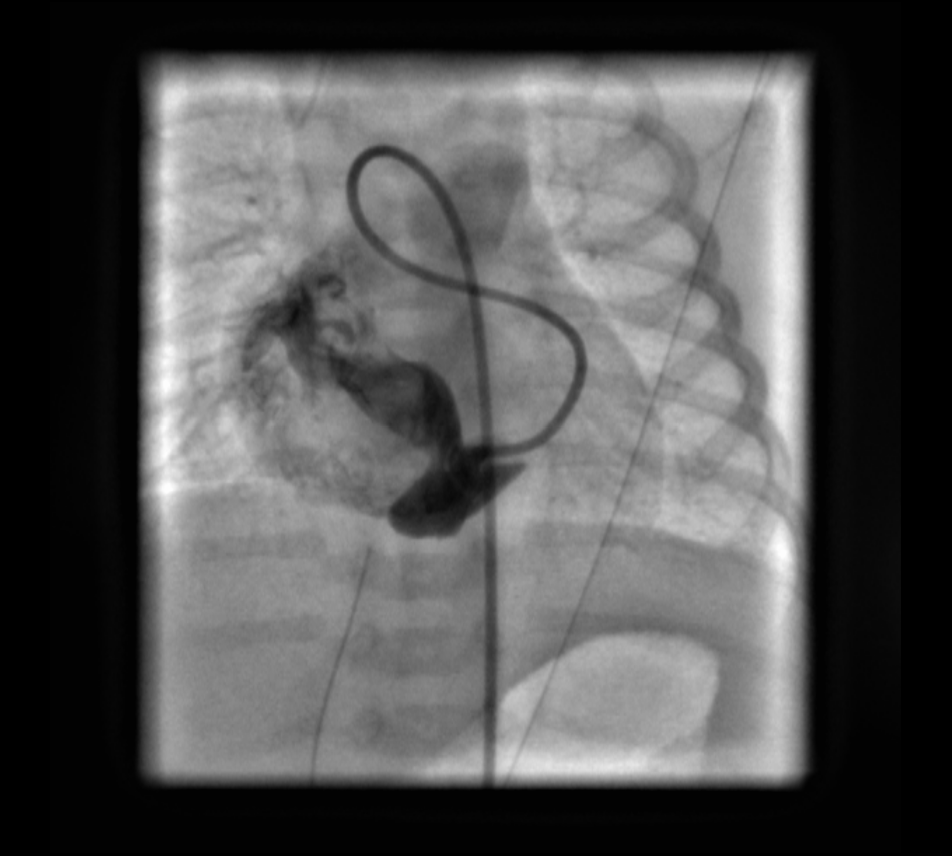

Coronary angiography revealed the fistulous connection to the coronary sinus off of the distal left circumflex coronary artery (LCX). Embolization of the fistula was performed using 2 coils (14 cm × 4 mm distally and 14 cm × 6 mm proximally). Repeated coronary angiography results confirmed the complete occlusion of the fistula and good filling of the left coronary artery (Figures 1-6, fluoroscopic anteroposterior views of the chest).

Figure 2. Angiographic view of the dilated LCX with contrast extension into the coronary sinus and the right atrium.